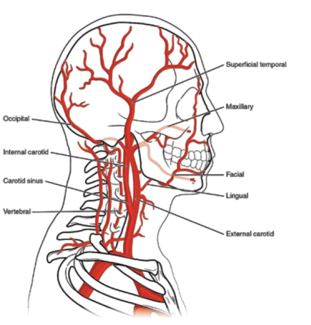

Mehmet Cilingiroglu, MD; Ibrahim Halil Inanc, MD

Maxillofacial injury is common following major facial trauma, and can lead to life-threatening hemorrhage. The branches of the external carotid artery (Figure 1) are most vulnerable to trauma as the vessels transverse bone structures. The...